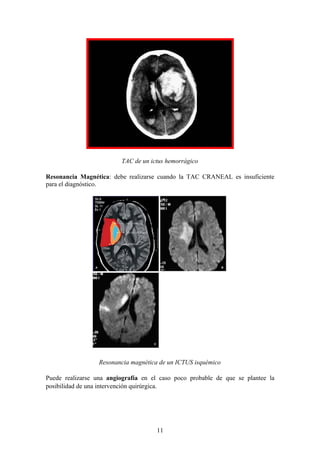

TAC de un ictus hemorrágico

Resonancia Magnética: debe realizarse cuando la TAC CRANEAL es insuficiente

para el diagnóstico.

Resonancia magnética de un ICTUS isquémico

Puede realizarse una angiografía en el caso poco probable de que se plantee la

posibilidad de una intervención quirúrgica.